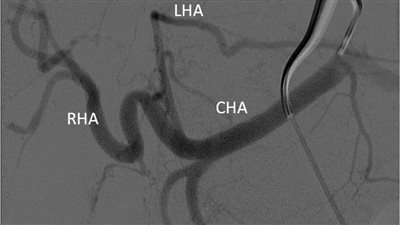

قسطرة بالشريان الكبدى

بنها الجامعي ينجح في حقن ورم كبدي كبير الحجم لمريضة من خلال قسطرة بالشريان